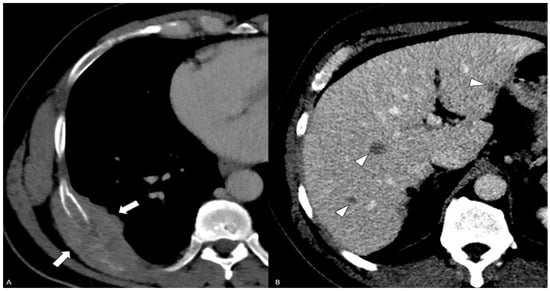

- Yang, J.; Xiao, L.; Gao, X.; Tang, Y.; Hu, S. Primary Adenosquamous Carcinoma of the Prostate With Multiple Heterogenic Metastases Demonstrated on 68Ga-PSMA and 18F-FDG PET/CT Imaging. Clin. Nucl. Med. 2024, 49, 180–181. [Google Scholar] [CrossRef] [PubMed]

| Azzi/2022 [1] | 62 | 3.11 | 3 + 3 = 6 (<10%) | N/A | rectum, lung | Ra, chemo | 9 | AWND |